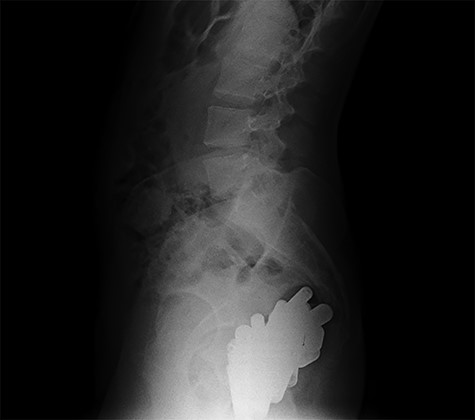

At hospitalization, the clinical examination revealed moderate pain in the lower left part of the abdomen. Laboratory analyses demonstrated moderate neutrophilic leukocytosis. Abdominal X-rays revealed the presence of many radiopaque foreign bodies on the projection of the rectum, referable to stylus batteries (Figs 1 and 2).

Erect abdominal X-rays (frontal view): presence of many radiopaque foreign bodies in the pelvis